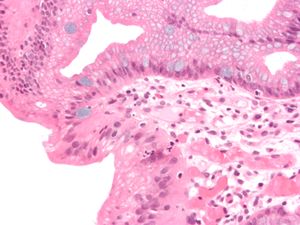

Micrograph of a gastro-esophageal junction with pancreatic acinar metaplasia. The esophageal mucosa (stratified squamous epithelium) is seen on the right. The gastric mucosa (simple columnar epithelium) is seen on the left. The metaplastic epithelial is at the junction (center of image) and has an intensely eosinophilic (bright pink) cytoplasm. H&E stain.

الحوؤل ( Metaplasia ) هو استبدال خلايا متمايزة ((differentiated cells من نوع معين بخلايا متمابزة من نوع آخر. الحوؤل مختلف عن خلل التنسج (dysplasia ) كما انه مختلف عن السرطان .

يؤدي الحوؤل إلى تغيير مآل الخلايا في مطلع حياتها ولا يغير الخلايا المتمايزة (differentiated cells).

الحوؤل عكوس (reversible ) وينجم عادة كاستجابة لالتهاب وتخريش مزمن ، ويتيح استبدال الخلايا باخرى اقدر على العيش في ظروف لاتحتملها الخلية الاصلية. و الحوؤل ليس ضارا في حد ذاته ولكنه يمكن أن يؤثر على بطانة اعضاء مختلفة كالقصبات (الطرق الهوائية) والمثانه. فالحوؤل في عنق الرحم يحدث تآكلا يمكن الكشف عنه باختبار لطاخة عنق الرحم.

الأهمية الطبية للحوؤل هي أن الخلايا قد تتطور من حوؤل إلى خلل تنسج ومن ثم إلى سرطان. و يحدث ذلك في مواقع عديدة من الجسم كالمثانه وعنق الرحم واسفل المريء. وعندما يكتشف الحوؤل في هذه المواقع ، نسعى سعيا جادا لازالة العوامل المسببة ، وبذلك نقلل من خطر ترقي الحوؤل إلى آفة خبيثة . ينبغي متابعة الناحية المصابة بالحؤول متابعة دقيقة لضمان كشف بدايات اي خلل تنسج الذي ان تطورت في العضو تطورا ملحوظا يستطب حينها ازالة المنطقة المصابة لمنع تطورها إلى سرطان.